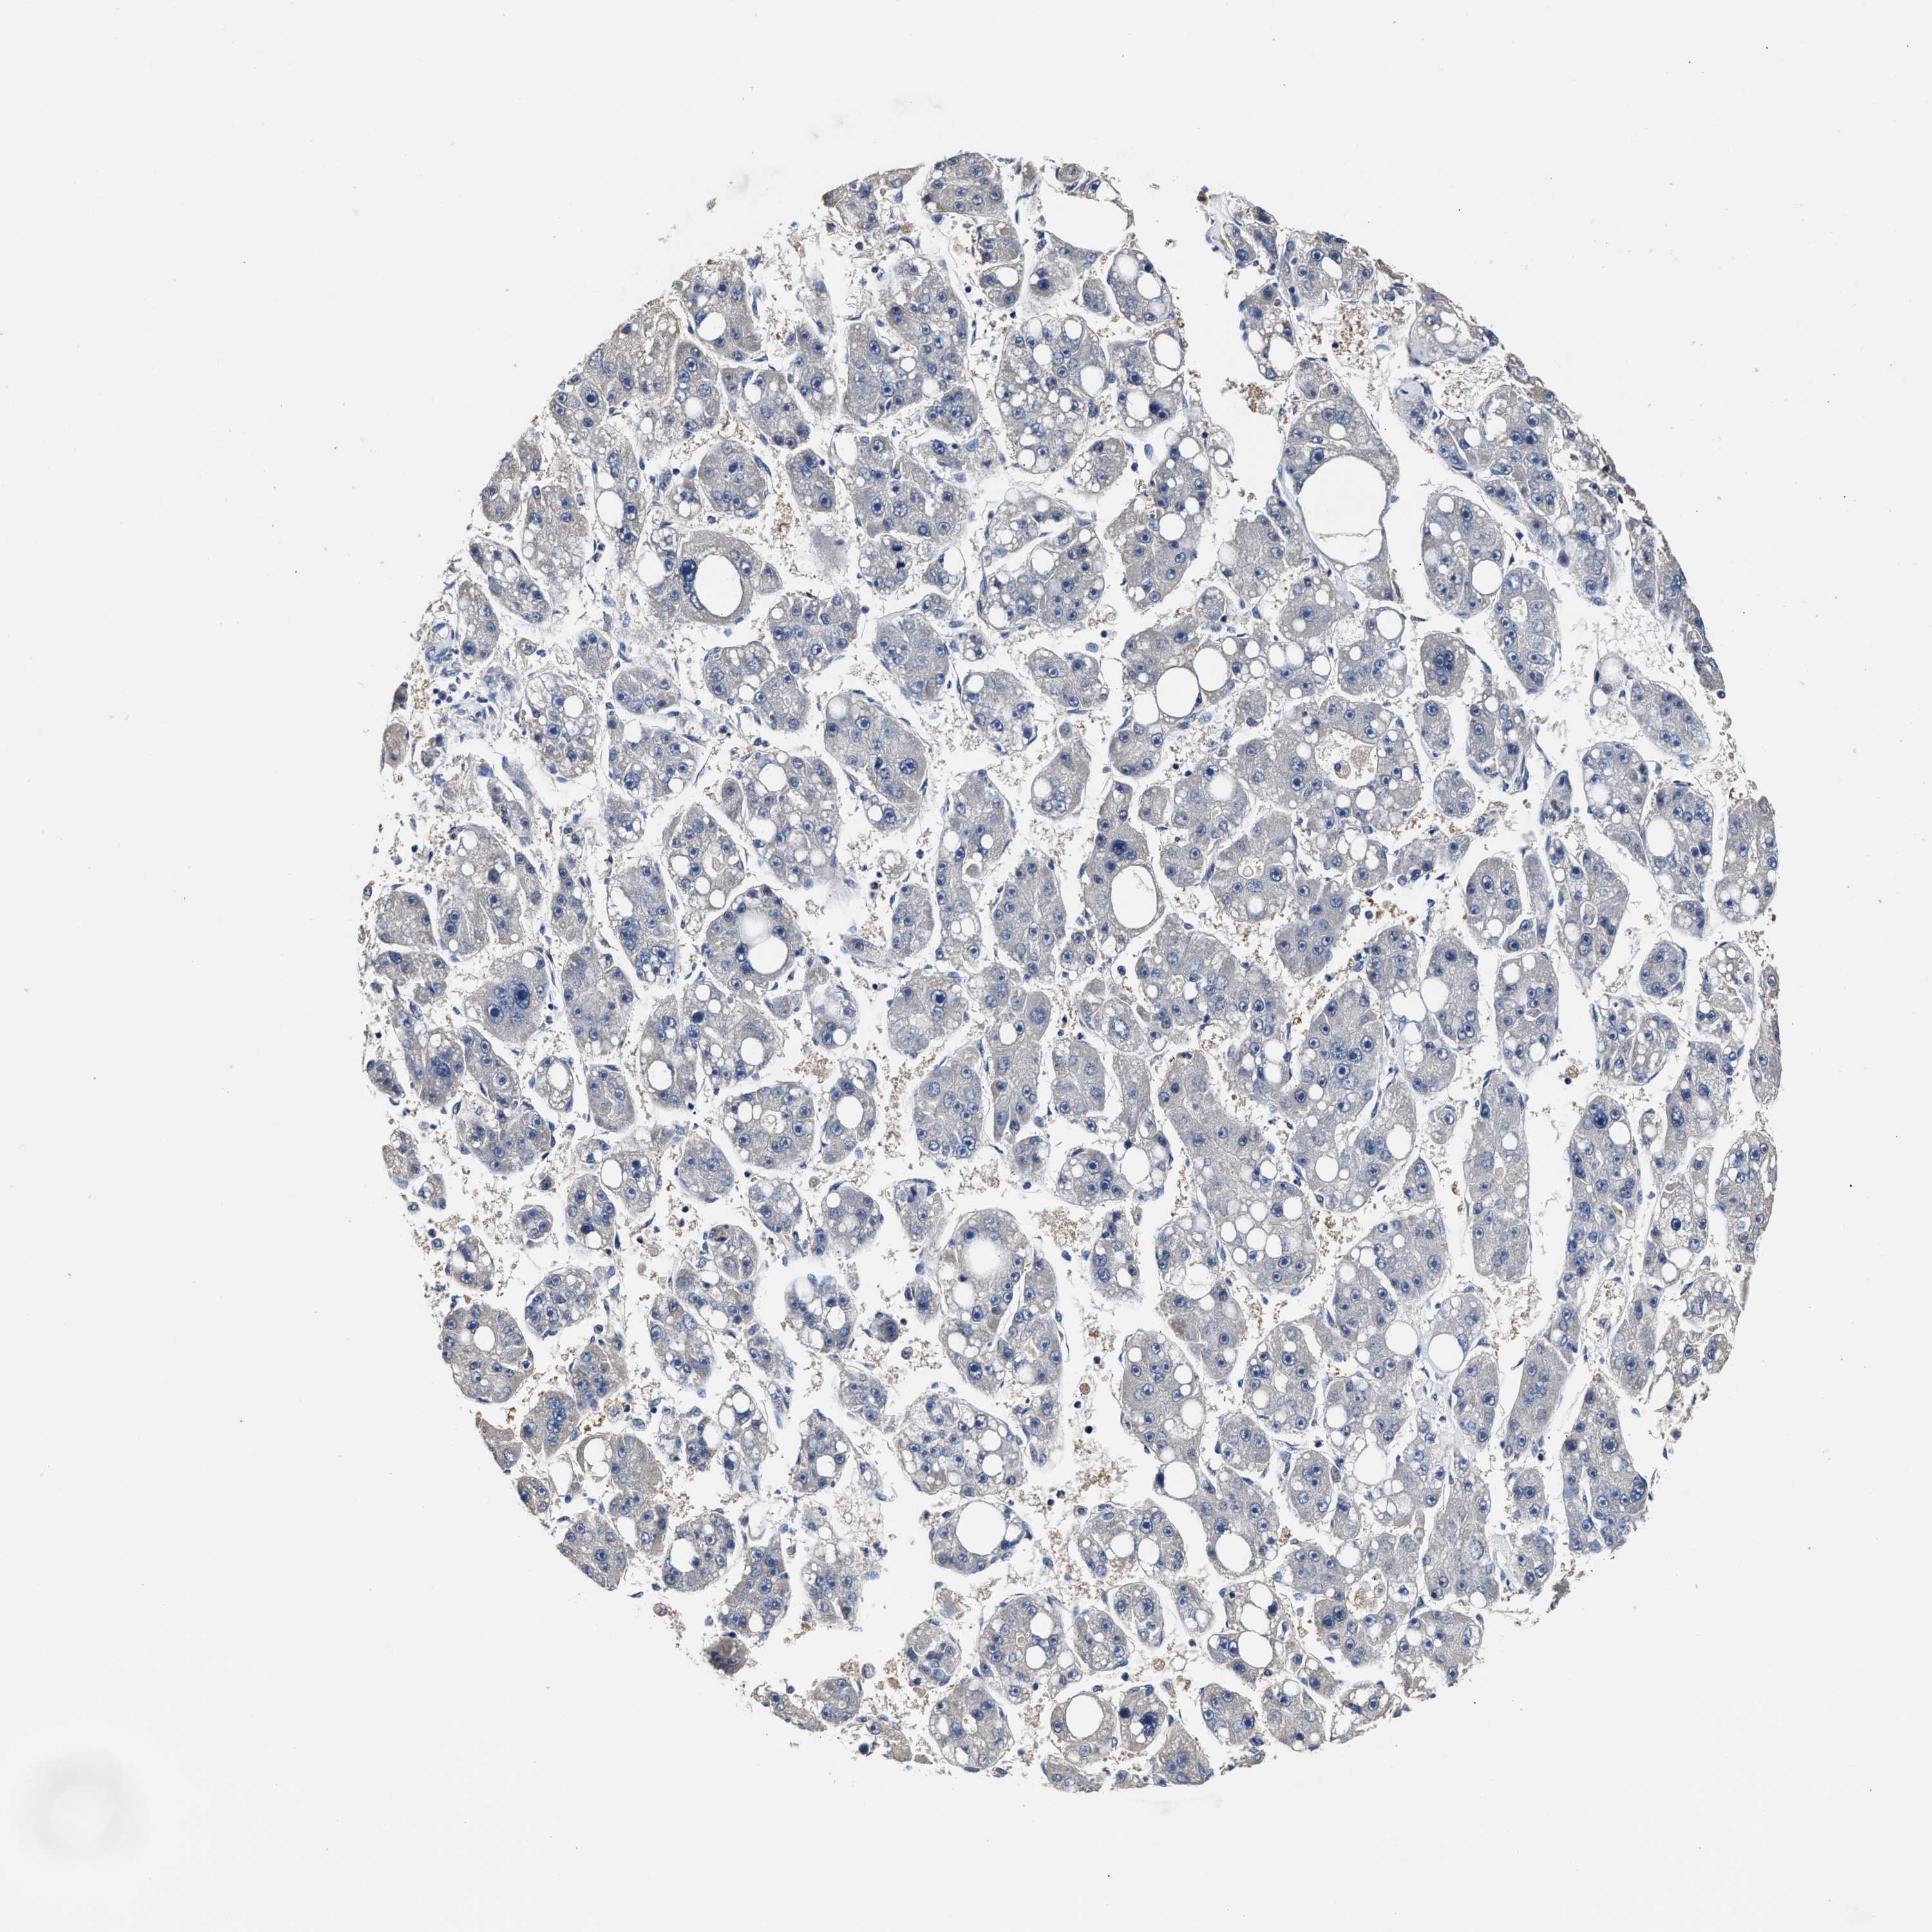

LIVER CANCER - Protein expressioni

A mouse-over function shows sample information and annotation data. Click on an image to view it in a full screen mode. Samples can be filtered based on level of antibody staining by selecting one or several of the following categories: high, medium, low and not detected. The assay and annotation is described here.

Note that samples used for immunohistochemistry by the Human Protein Atlas do not correspond to samples in the TCGA dataset.

Antibody stainingi

Antibody staining in the annotated cell types in the current human tissue is reported as not detected, low, medium, or high, based on conventional immunohistochemistry profiling in selected tissues. This score is based on the combination of the staining intensity and fraction of stained cells.

Each image is clickable and will lead to virtual microscopy that enables deeper exploration of all samples and also displays staining intensity scores, fraction scores and subcellular localization as well as patient and tissue information for each sample.

HPA048652

HPA055972

HPA055973

CAB022669

CAB047357

Cholangiocarcinoma

Carcinoma, Hepatocellular, NOS